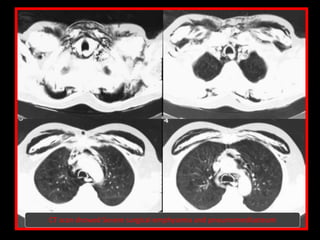

Subcutaneous emphysema

CT scan showed Severe surgical emphysema and pneumomediasteum